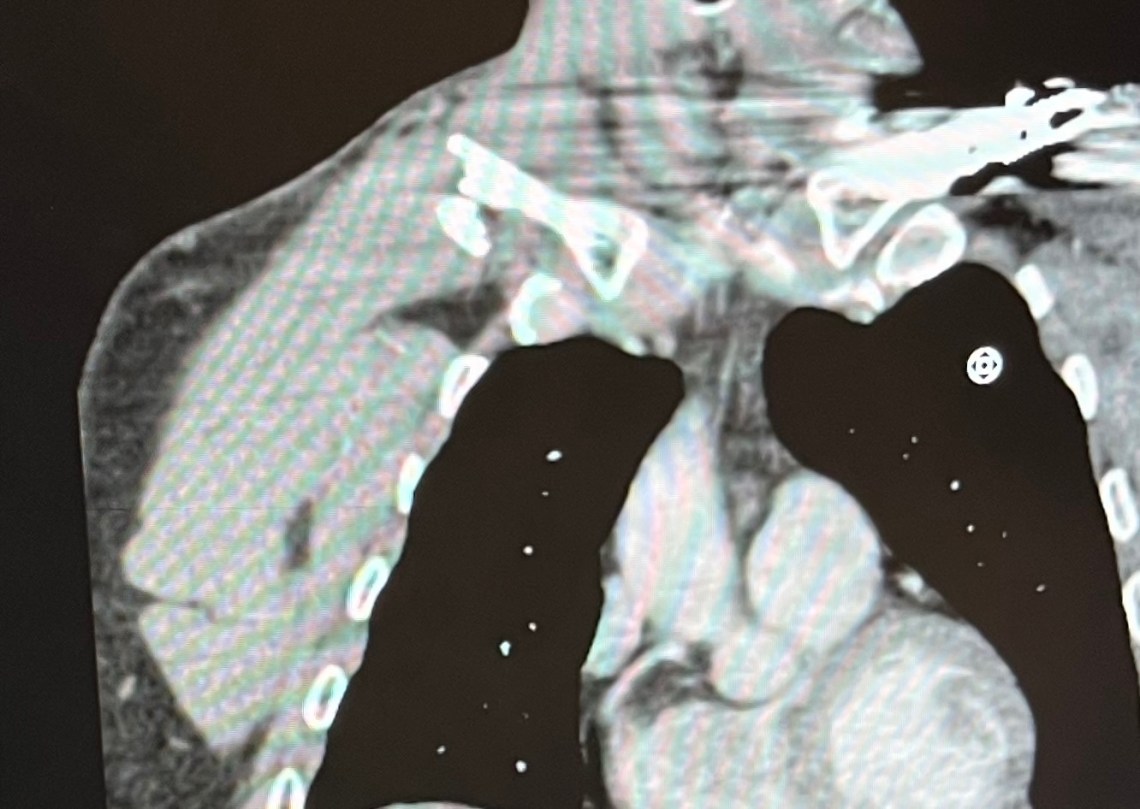

I had to pee. After my off, that evening in X-ray at UPMC, 331 milliliters worth. (Perversely, I took a picture (below). Moderate-yellow but not shockingly so. I rule out dehydration as a cause for any passing-out.